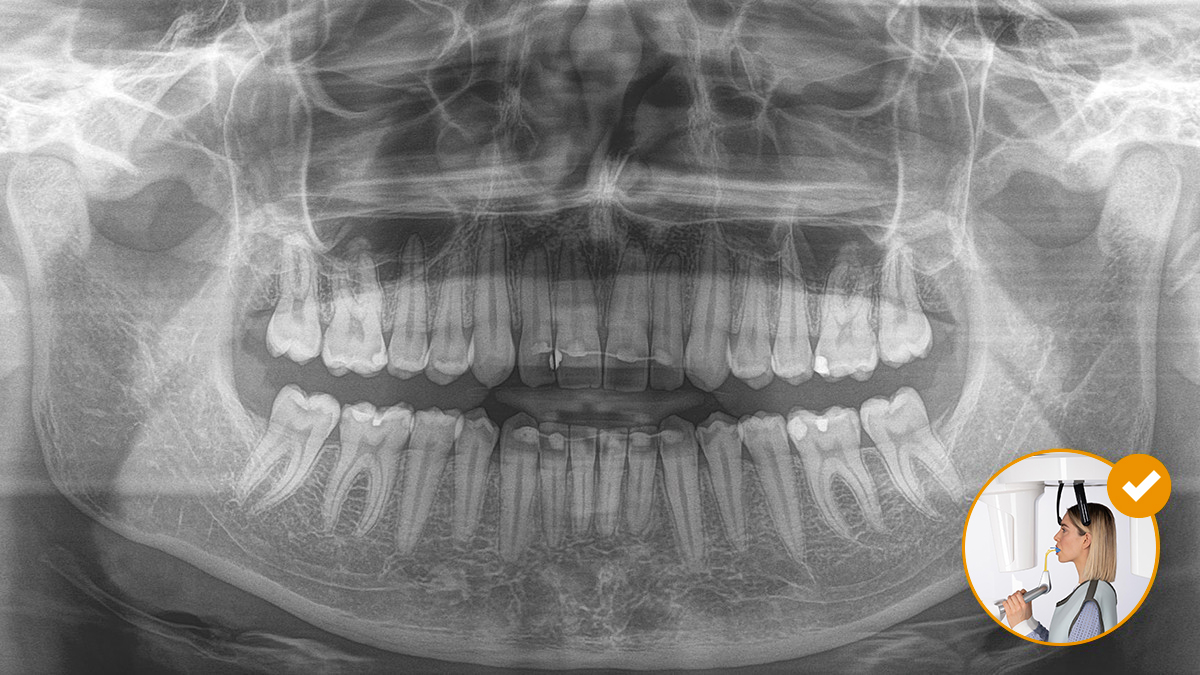

Correct patient positioning leads to high image quality to support an accurate diagnosis and facilitates and improves patient experience.

This is our 10-point concept for easy patient positioning and X-ray imaging. It is primarily about two things: high image quality and comfort for the patient and the assistant.